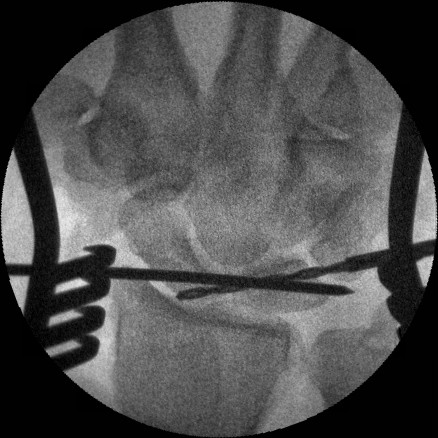

Intraoperative correction of scapholunate rotation using K-wires as joysticks on each bone.

Click for larger image